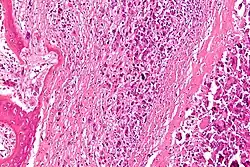

Een bottumor of beentumor is een plaatselijke abnormale groei van cellen in het bot. Bottumoren (of botgezwellen) kunnen goedaardig (benigne) zijn of kwaadaardig (maligne).

Een tumor heet kwaadaardig als hij de eigenschap heeft om in te groeien in het omliggende weefsel (infiltratie) en uit te zaaien (metastasering).

Kankers die beginnen in de botten worden primaire bottumoren genoemd. Kankers die beginnen in een ander deel van het lichaam (zoals de borst, longen of darmen zijn voorbeelden van secundaire of gemetastaseerde botkanker; die gedragen zich heel anders dan primaire bottumoren. Multipel myeloom verspreidt zich ook door het bot, maar is een ziekte van het beenmerg en wordt niet beschouwd als een primaire bottumor.